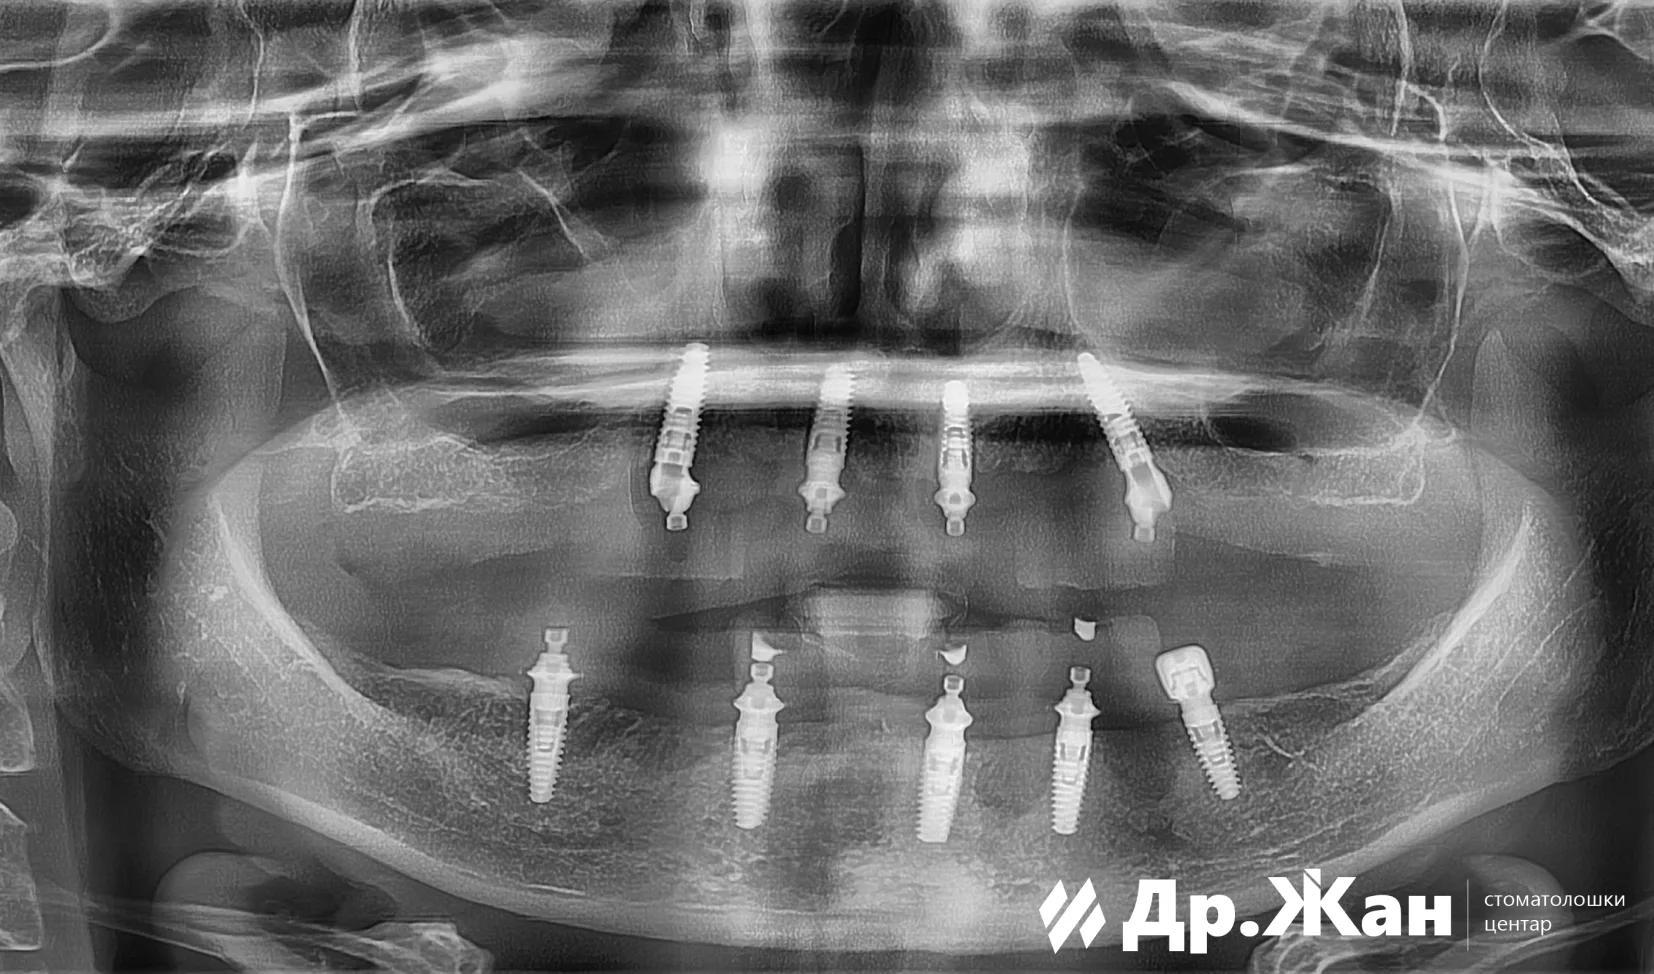

По прегледот и сите анализи, планот за терапија се состоеше од целосна реконструкција на устата со забни импланти. Сите заби беа отстранети, а имплантите беа поставени веднаш. На пациентката ѝ беа поставени привремени заби за време на периодот на заздравување.

По 6 месеци остеоинтеграција на забните импланти, обезбедивме нова прекрасна насмевка со хибридна конструкција, циркониум на титаниумска шипка.

ПОТОА

Вертикалната димензија на оклузијата беше подигната, па не само што добивме нова насмевка, туку резултатите се појавија на кожата на пациентката, постигнувајќи помлад и посвеж изглед.

Дигиталниот работен тек ни овозможи да го постигнеме овој прекрасен резултат. Се стремиме да ги користиме сите достапни алатки за да постигнеме предвидливи резултати како овој.